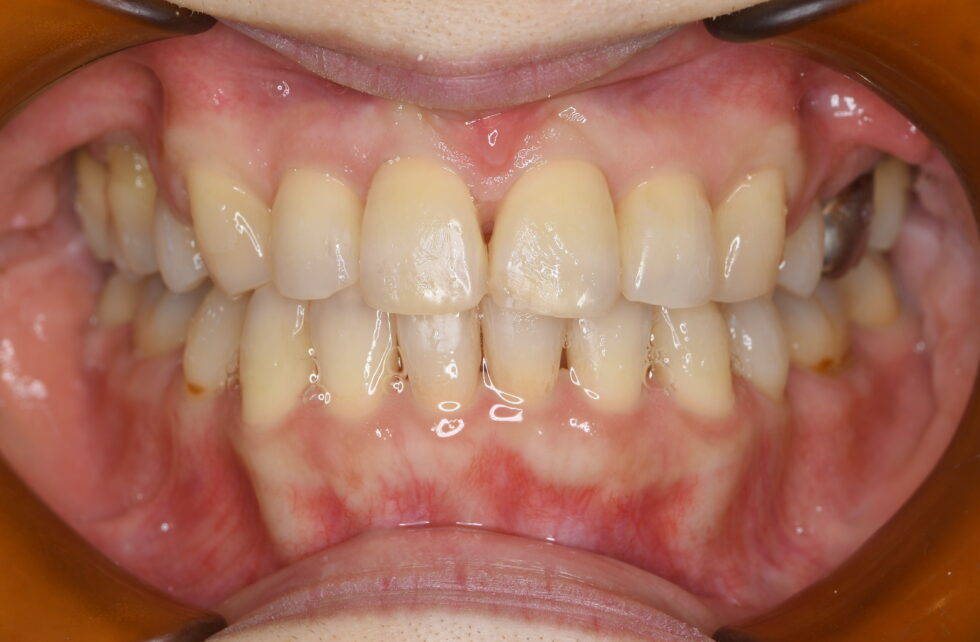

上顎左右側中切歯が前方へ傾斜するように突出し、側切歯は捻転して口蓋側へ転位していた。鼻唇角は90度を少し下回り、閉唇時にはオトガイ部の著しい緊張が見られた。セファロ分析の結果、下顎の後退を少々認めるが、上下顎前突として上下顎小臼歯抜歯を行っていただき、マルチブラケット装置を使用し矯正用アンカースクリューを併用して叢生の改善、前歯の後退を行った。前歯の後退が十分行われ、口元の突出や閉唇時のオトガイ部の緊張は改善した。動的治療期間2年9カ月 治療費の目安90万円程度